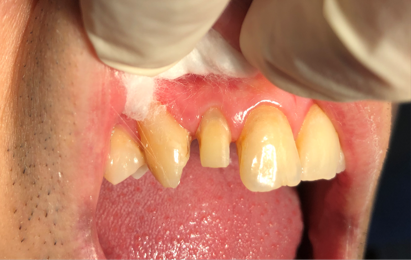

Root canal obturation

1/6/2025,post placement,tooth preparation,impression taking

1/16/2025: All-ceramic crown restoration for #12; patient asymptomatic